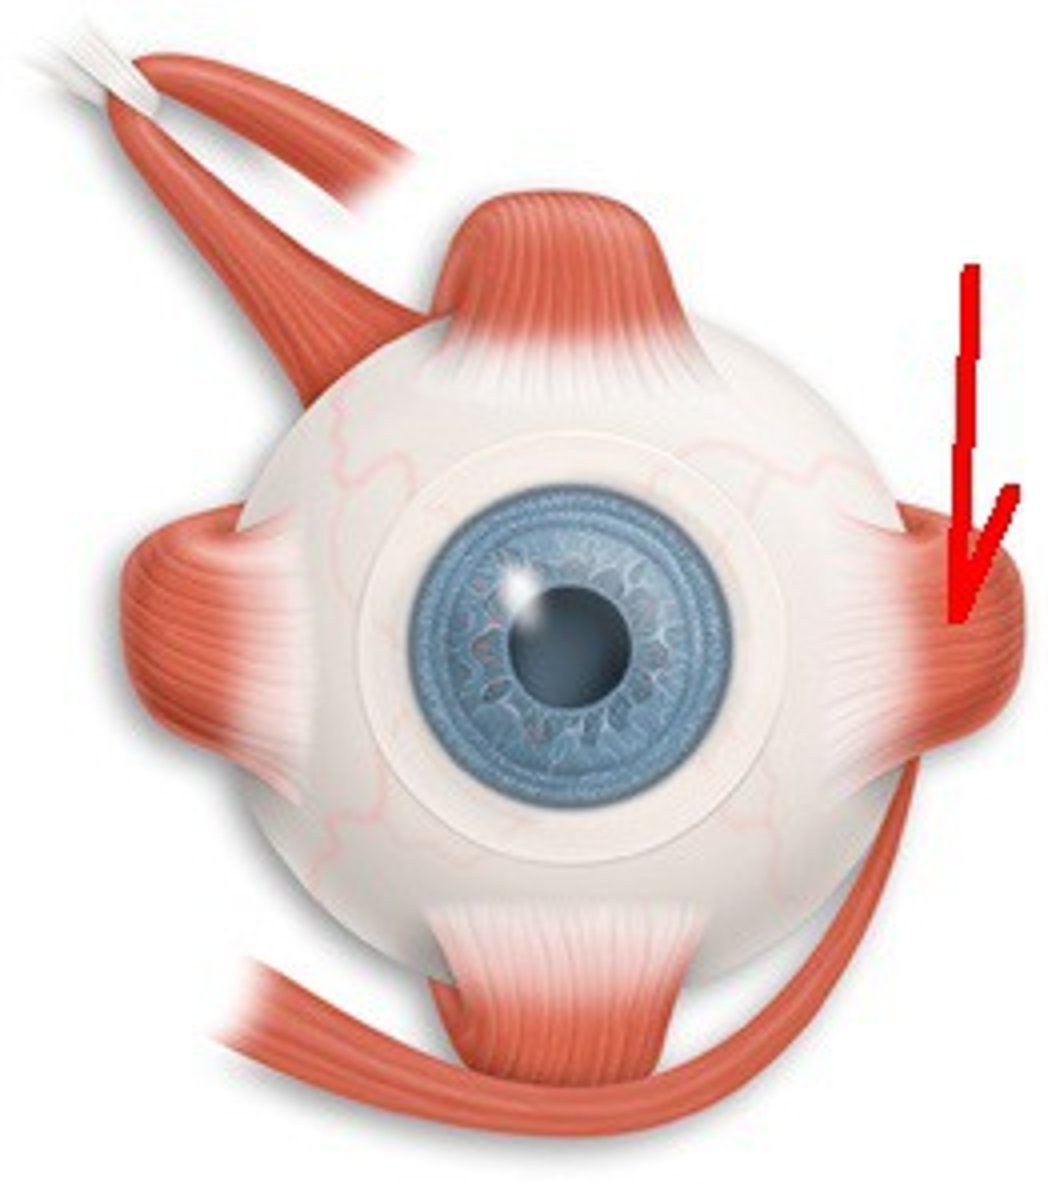

Superior Oblique

A muscle originating in the upper, medial side of the orbit which abducts, depresses and internally rotates the eye

Inferior Oblique

An extraocular muscle, and is attached to the maxillary bone (origin) and the posterior, inferior, lateral surface of the eye

Superior Rectus

One of the extraocular muscles. It elevates, adducts, and helps intort (rotate medially) the eye.

Inferior Rectus

An extraocular muscle. Depresses eye and turns it medially.

Lateral Rectus

A muscle on the lateral side of the eyeball in the orbit

Medial Rectus

The largest of the eye's extraocular movement muscles; adducts the eyeball